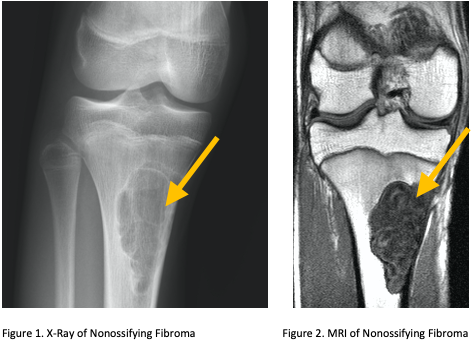

• • Imaging includes X-rays, MRI, CT and PET Scans may also be used as well as bone scans.

Radiographic imaging is used to help form a diagnosis. These include X-Ray, MRI, CT and Bone Scans

An example of a X-Ray and MRI are shown.